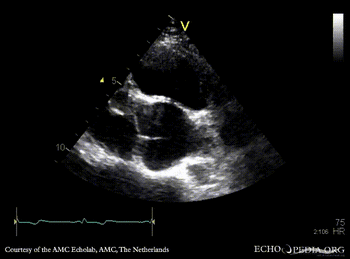

PSAX: redundant mitral valve leaflets